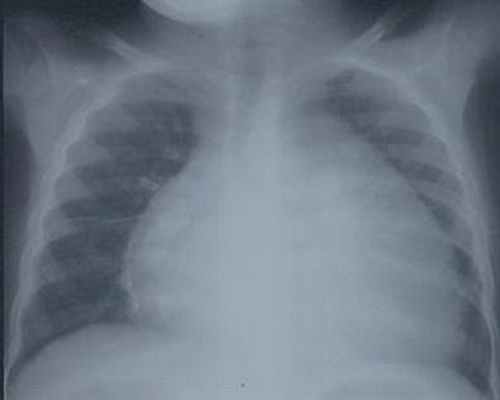

- рентгенография органов грудной полости – может показать расширение тени сердца в связи с гипертрофией миокарда или дилатацией желудочков, изменения в нижних отделах легких или по всем легочным полям (признаки венозного застоя или отека легких соответственно).

На рентгенограмме органов грудной клетки видно увеличение всех камер сердца, называемое кардиомегалией.